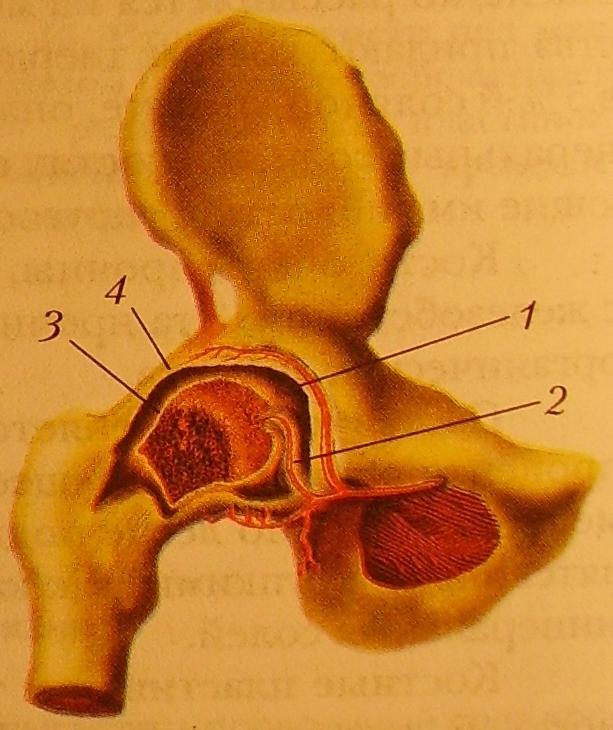

Рисунки Суставов: Анатомические Иллюстрации